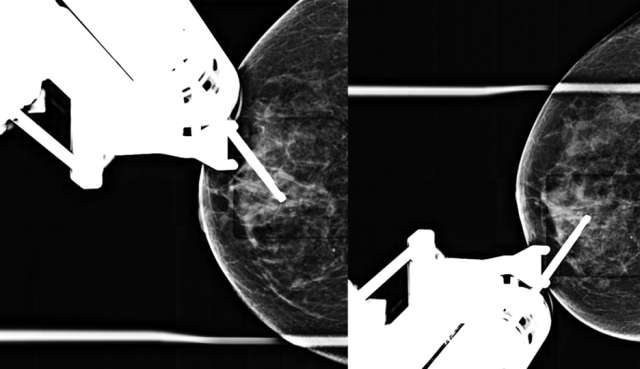

• Technologist takes a stereotactic pair of images (+/- 15 degrees) and radiologist confirms accurate trajectory (Figure 3).

Figure 3. Prefire stereotactic pair of CC images taken +/- 15 degrees.

• Technologist repeats stereotactic pair (+/- 15 degrees) and radiologist confirms accurate trajectory on the postfire images (Figure 4).

Figure 4. Postfire stereotactic pair of CC images taken +/- 15 degrees oblique.